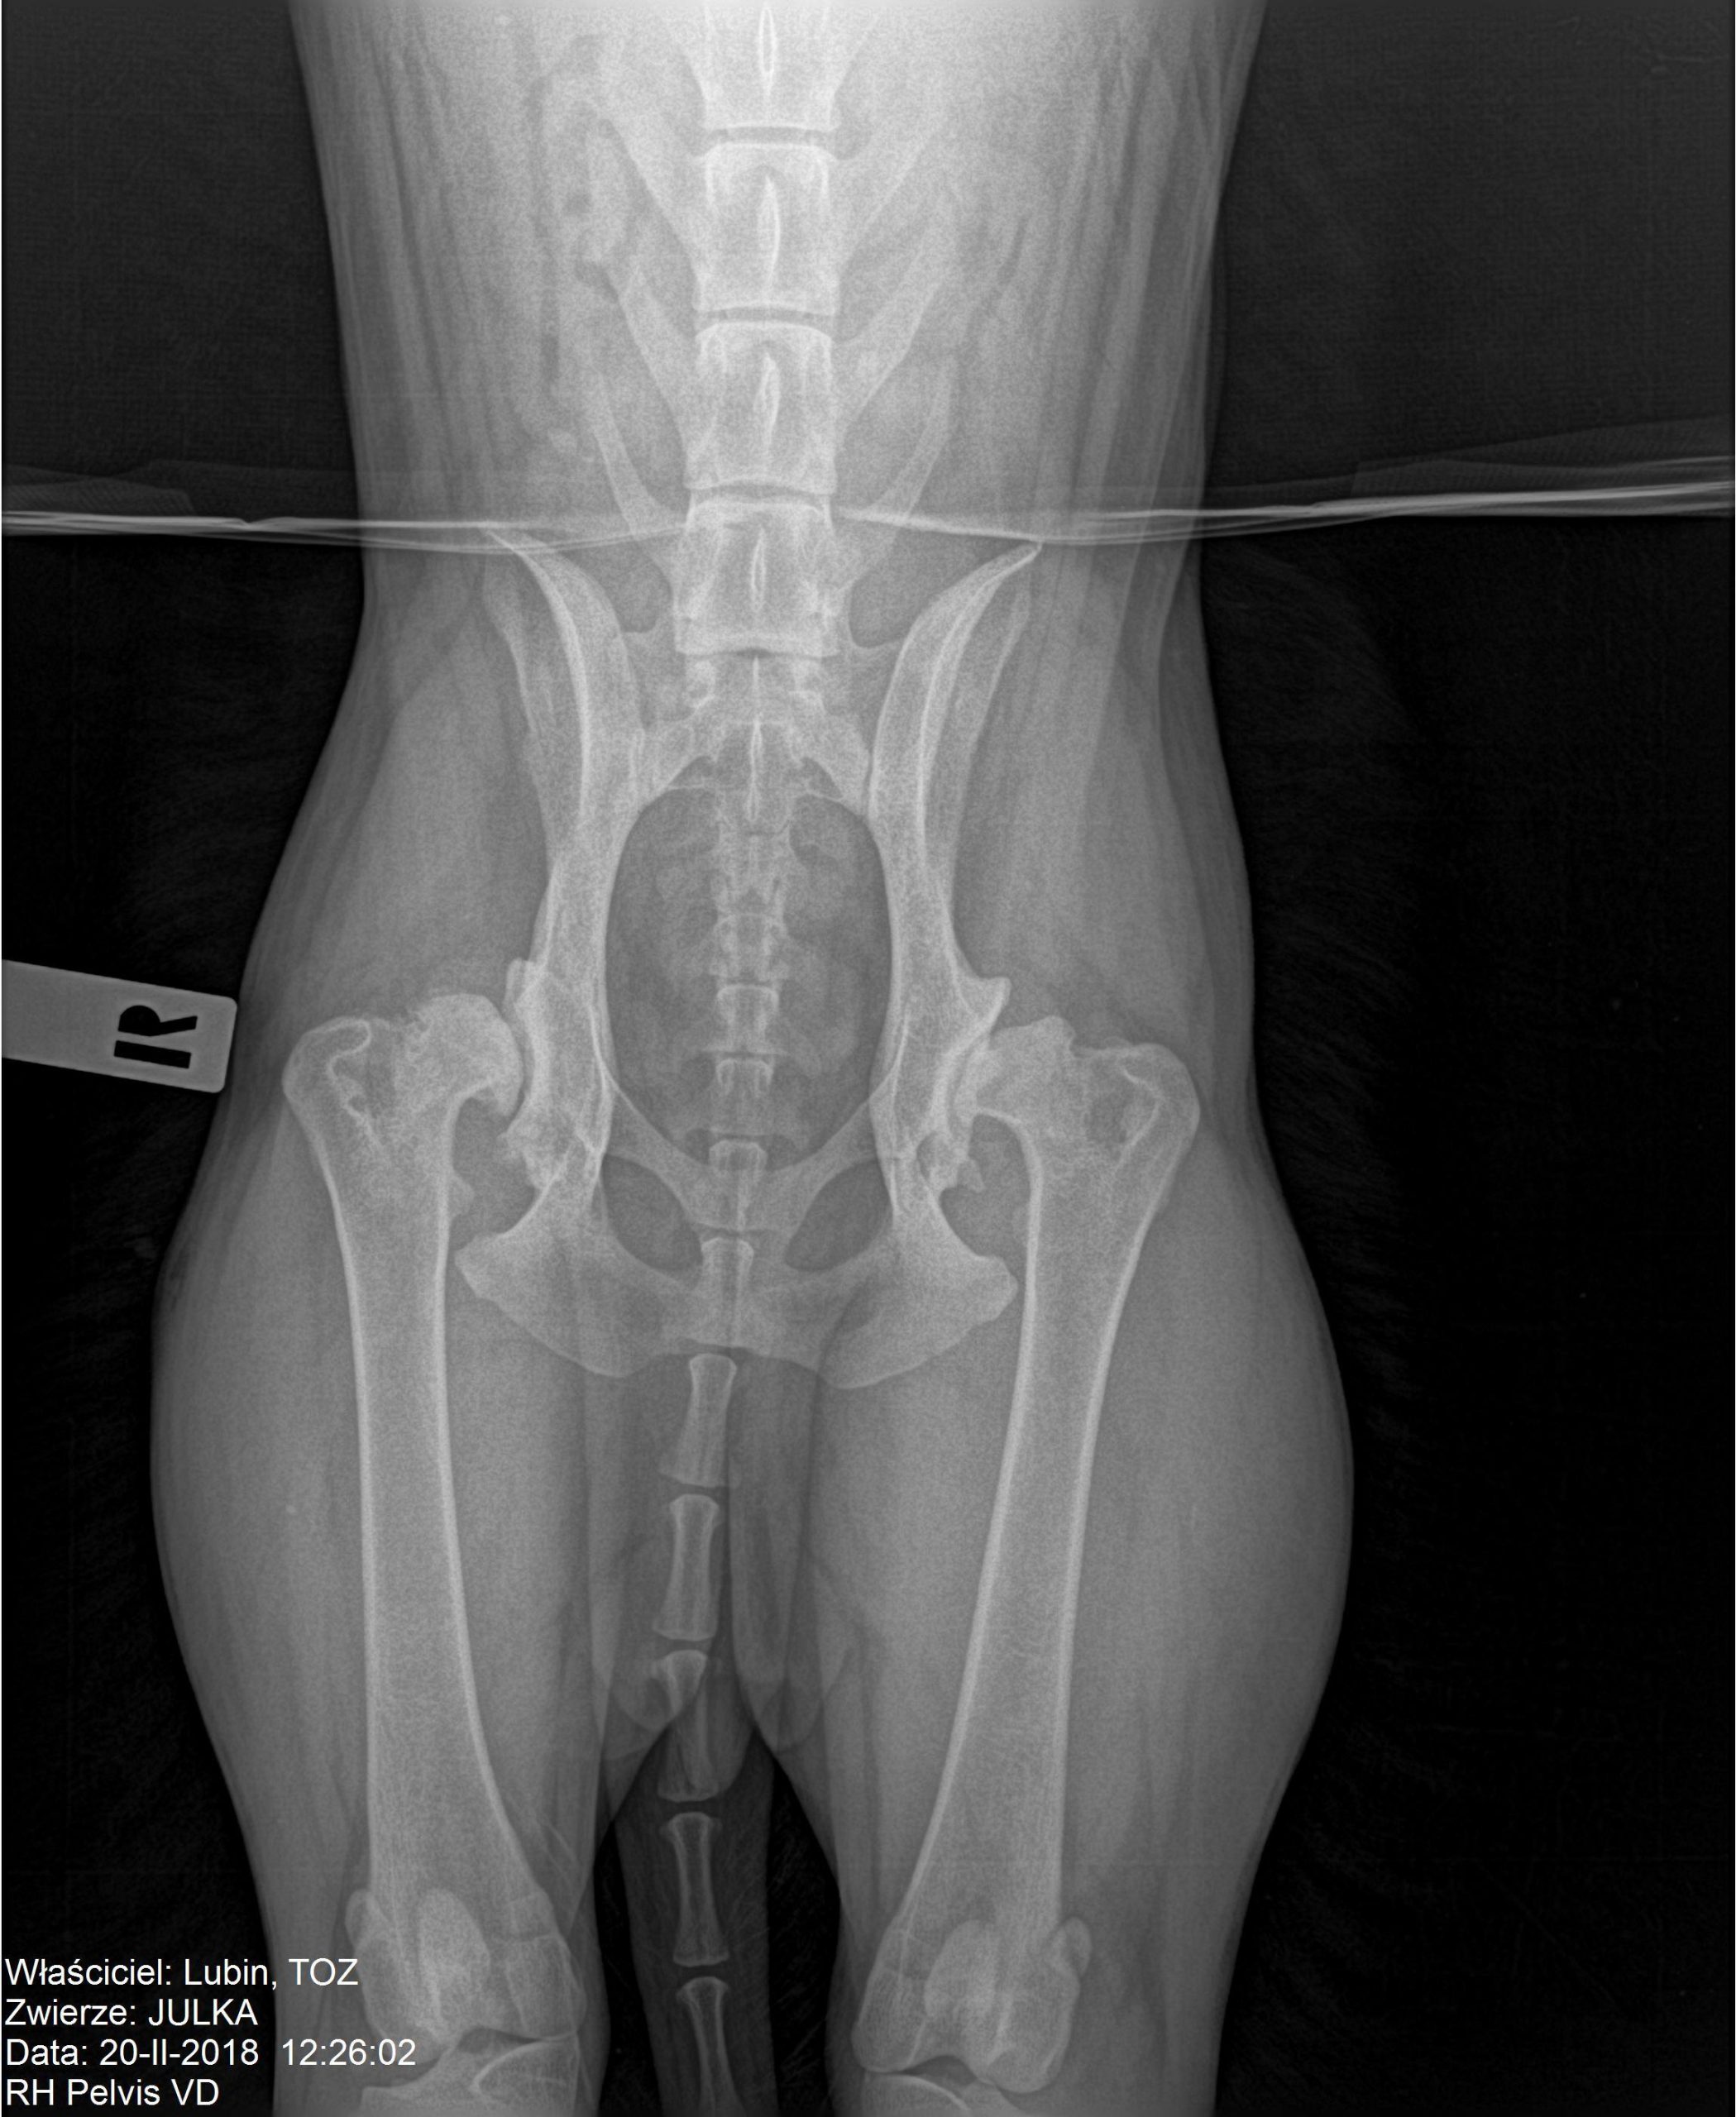

Wracamy do znanej czytelnikom Julki. TOZ ponownie zbiera fundusze na pomoc dla suczki. Julka żyje w ciągłym bólu – problemy z biodrami utrudniają jej bieganie i skakanie. U psiaka zdiagnozowano bowiem dysplazję stawów biodrowych. Dodatkowo ma silną anemię i szybko traci na wadze. Początkowo planowano przeprowadzenie operacji, ale teraz nadarzyła się inna szansa na odzyskanie zdrowia – syntetyczna wiskoproteza.

Niestety stan zdrowia suczki od początku był zły. Julka wymagała długiego procesu leczenia i opieki profesjonalistów. Na początku 2017 r. trafiła do hoteliku w Warszawie, gdzie miała mieć zapewnioną opiekę behawioralną oraz weterynaryjną. Tam zdiagnozowano u suczki ciężką dysplazję stawów biodrowych oraz bardzo silną anemię.

– Julka dziś jest piękną, łagodną 25-kilogramową kuleczką. Jej wdzięczność za nowe życie powala na kolana. Suczka odzyskała równowagę emocjonalną, ale wciąż przeszkodą są problemy natury fizycznej. Dysplazja stawów biodrowych utrudnia suni bieganie, skakanie i inne czynności. Wcześniej sądziliśmy, że będzie musiała przejść operację. Teraz znaleźliśmy nowe rozwiązanie – opowiada Karolina Lorenc.

Pomoc dla Julki czeka na nią w Gdańsku lub bliżej – we Wrocławiu. Nowa metoda Noltrex to syntetyczna wiskoproteza o właściwościach podobnych do mazi stawowej. Jej bardzo wysoka gęstość wspomaga amortyzacją stawu, zapobiegając otarciom, niwelując ból, a zawarte w niej jony srebra działają bakteriostatycznie. Wiskoproteza pomaga zachować integralność chrząstki stawowej, co jest szczególnie istotne w przewlekłych chorobach zwyrodnieniowych.